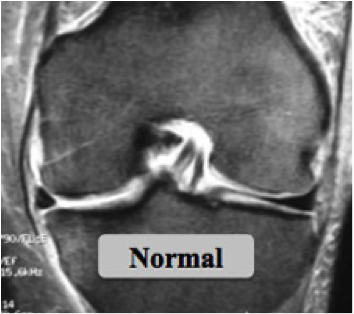

Les ménisques sont des fibrocartilages semi-lunaires triangulaires à la coupe, dont le rôle est principalement d’amortir, comme des semelles de chaussures, de protéger les cartilages du fémur et du tibia.

Compte-tenu de la forme arrondie du fémur, les ménisques sont importants dans la congruence articulaire, c’est-à-dire, à donner la stabilité du genou avec les ligaments croisés.

Ils ont un ancrage osseux par leurs cornes antérieures et postérieures, liées aux surfaces pré- et rétro-spinales et un ancrage capsulo-ligamentaire par le bord périphérique circonférentiel.

Les ménisques agissent comme des "calles" pour stabiliser le fémur (rond) sur le tibia (plat).